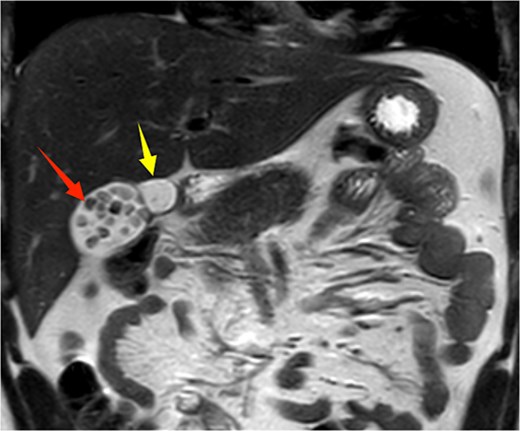

Given the patient’s recurrent biliary colic, laparoscopic cholecystectomy was decided. During surgery, adhesions between the gallbladder and the surrounding omentum were carefully dissected. After mobilizing the hepatic porta, the anatomy of Calot’s triangle was meticulously identified, confirming the double gallbladder malformation as preoperatively suspected. The two gallbladders had independent cystic ducts draining into the common hepatic duct (Fig. 3). The lateral gallbladder contained multiple stones, while the medial one was stone-free. A single cystic artery, originating from the right hepatic artery, was observed passing posteriorly between the two cystic ducts before supplying the gallbladders. The cystic ducts were sequentially clipped and transected using bioabsorbable clips. Postoperative specimen dissection revealed two gallbladders measuring 8.5 × 3.0 cm and 8.5 × 2.5 cm, respectively. The serosal surfaces of the two gallbladder bodies were adherent, and each had an independent cystic duct inserting into the common hepatic duct, confirming an "H-type" double gallbladder malformation (Fig. 4). Pathological examination reported a double gallbladder malformation: one with a slightly roughened mucosa, wall thickness of 0.2 cm, multiple stones, and features of adenomatous cholecystitis; the other with a smooth mucosa, wall thickness of 0.1 cm, and no significant stones. The patient recovered well and was discharged on the first postoperative day.

Intraoperative image showing two cystic ducts, each indicated by an arrow.